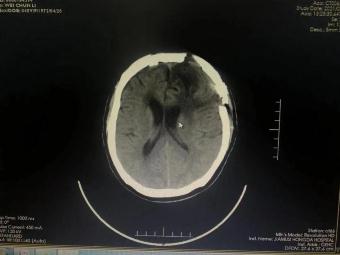

手術(shù)前 手術(shù)后

術(shù)前神經(jīng)外科與麻醉科、手術(shù)室、輸血科等科室反復(fù)認(rèn)真研究,制定了精細(xì)的手術(shù)方案和應(yīng)急預(yù)案。2月23日手術(shù)如期進(jìn)行并成功順利完成。術(shù)后第一日,患者神志清、言語(yǔ)明,對(duì)答問(wèn)題流利切題;查體配合,右側(cè)肢體肌力明顯增強(qiáng),生命指征平穩(wěn)。術(shù)后在神經(jīng)外科護(hù)理團(tuán)隊(duì)的精心護(hù)理下,患者恢復(fù)良好,可正常離床活動(dòng),目前已經(jīng)康復(fù)出院。